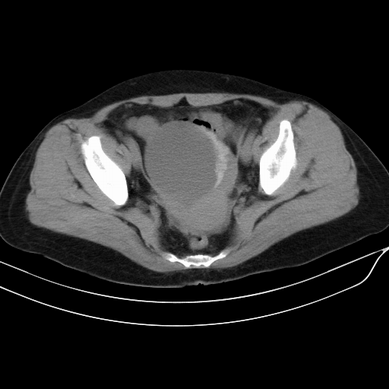

以下是引用zsl6918在2008-6-5 13:49:00的发言:[br]右侧附件区囊性占位,边可见钙化改变,底可见实性结节,考虑囊腺瘤可能性大.

以下是引用zjzjr在2008-6-5 17:29:00的发言:[br]可见壁结节,支持囊腺瘤可能性大.